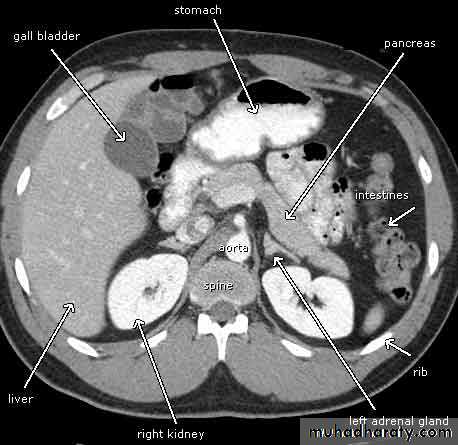

CT abdomen

Pancreatitis

Patient present with abdominal pain , vomiting with or without jaundice , increase amylase level

CT finding

Enlargement of the pancreas focal or generalized increase in size .

Hypo density within the pancreas focal or generalized due to the edema .

Peri pancreatic fluid collection & edema around the pancreas .

The fluid around the pancreas if persist more than 6 w become encysted leading to the pancreatic pseudo cyst any area could be affected .

Edema of the wall of the stomach .